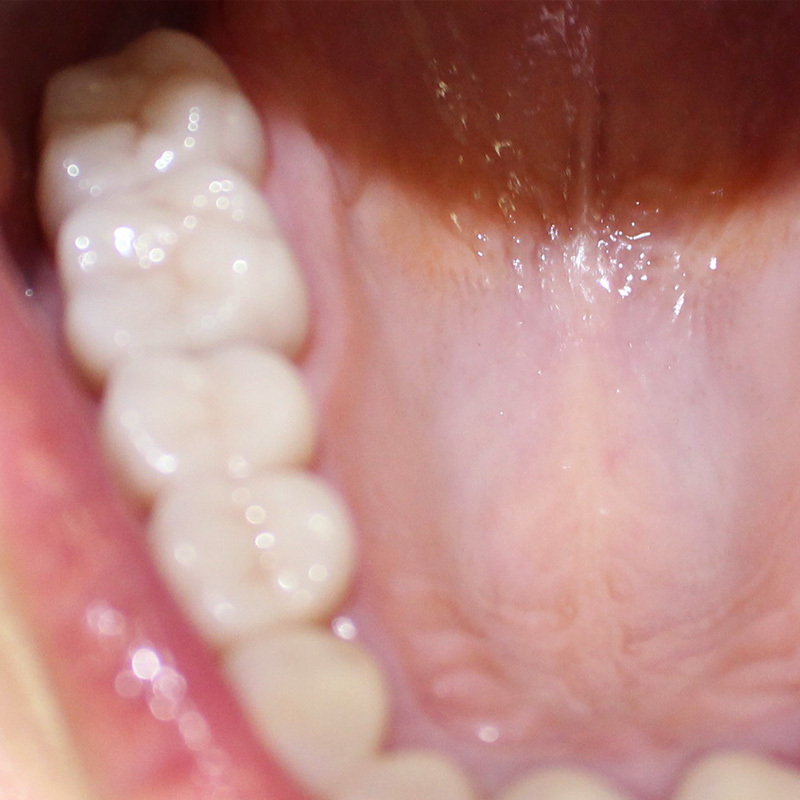

До и после лечения

После осмотра и тщательной диагностики врач-ортопед Мельников Алексей Владимирович предложил протезирование коронками из цельной керамики.

Керамические коронки идеальны для высокоэстетичных реставраций в зоне улыбки. Керамика не выделяется в полости рта и обладает естественной светопрозрачностью.

- изготовление и установка цельнокерамических коронок на 15-17 зубы.